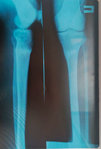

Исходник - 38 лет.

Дата операции - 07.11.2019г.

Диагноз: Варусная деформация голеней. Ротация справа.